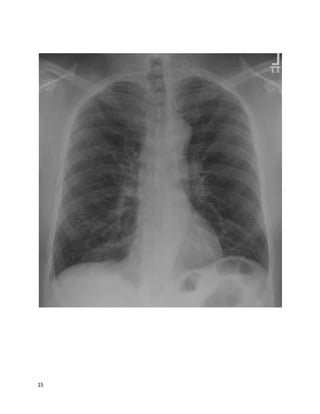

This 78 year old white woman has been coughing for "a good while"; you estimate

at least many months by her history. She is persistently fatigued, has lost 5 pounds,

but has no fevers or night sweats. She is a never-smoker. She sometimes coughs up

blood-streaked sputum. She lives in a high-rise retirement home. Other cuts of her

chest CT are similar to the one below, correlating well with the findings on chest

X-ray.

3

4